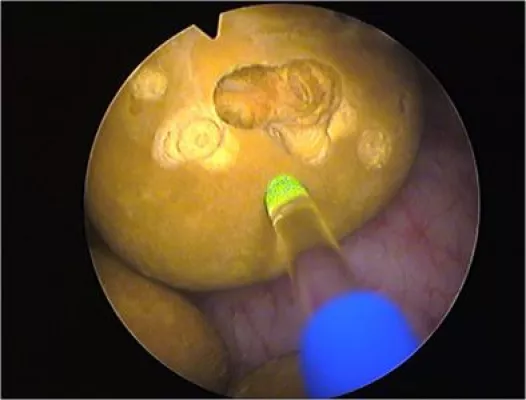

Der unsichtbare Infrarot-Laserstrahl gelangt durch einen besonders geformten Glasfaser-Lichtleiter an den „Ort des Geschehens“. Dort berührt die abgeflachte Spitze das Gewebe und erreicht so eine noch genauere Gewebeabtragung im Vergleich zu konventionellen Laserbehandlungen. Mit dem Dual-Laser können Strukturen im Innern der Prostata geschont werden, die den Samenerguss ermöglichen.

Bei der Behandlung der gutartigen Prostata-Vergrößerung, der so genannten Benignen Prostata-Hyperplasie (BPH) setzt die Klinik neuerdings auf ein besonderes Laserverfahren, das sich vor allem an Patienten mittleren Alters richtet, denen es wichtig ist, auch nach einer Prostata-Behandlung einen vollwertigen Samenerguss zu haben. Das erfordert eine punktgenaue, präzise Laserbehandlung der Prostata, wie sie mit dem so genannten Evolve-Dual-Laser des deutschen Unternehmens Biolitec aus Jena möglich ist.

Der Laser arbeitet im Infrarotbereich und hier mit zwei parallel zu betreibenden Wellenlängen von 1470 und 980 Nanometern (nm). Das hat den Vorteil, dass eine optimale Absorption in Hämoglobin erzielt wird. „Damit erreichen wir eine hohe Ablationsrate bei gleichzeitig guter Hämostase“, erklärt der Urologe Dr. Joachim-Ernst Deuster. Im Klartext: das wuchernde Prostata-Gewebe wird rasch und effektiv abgetragen und der aufgestaute Urin kann wieder ungehindert abfließen. Direkt nach der Behandlung fühlt sich der Patient erleichtert und verspürt nicht mehr den ständigen und lästigen Harndrang. „Die gute Hämostase wirkt sich positiv auf den Heilungsprozess aus“, ergänzt Mitgesellschafter der Klinik, der Urologe Dr. Thomas Dill. Es entstehe praktisch kein Blutverlust und das umliegende Gewebe werde geschont.